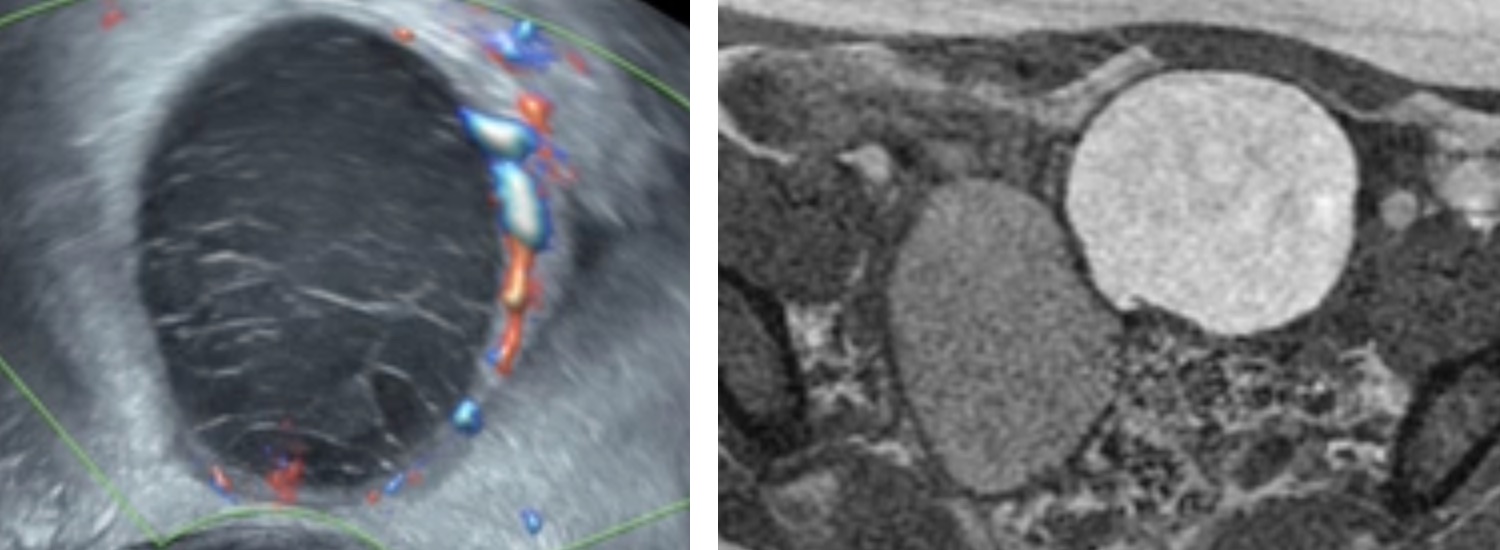

Endométriome (implant hémorragique si ≤ 1 cm, aspécifique si isolé)

- écho : fin piqueté échogène homogène, spots pariétaux hyper, ± septas, multiples++

- ± niveau liquide-liquide, caillot (déclive, mobile, avasculaire), hématosalpinx

- IRM : HT1 ≥ graisse, shading en T2 (HT2 20% voire hT2 si ancien)

DD KLH : couronne hypervascularisée et HT1 < graisse

DD KLH : couronne hypervascularisée et HT1 < graisse